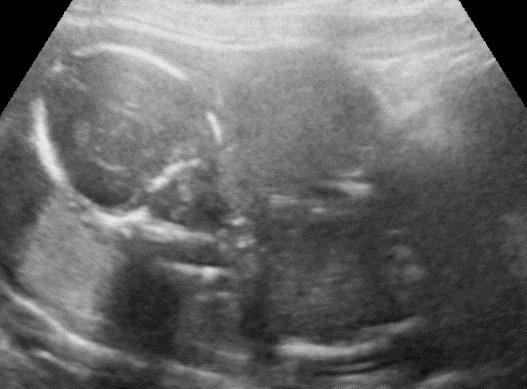

川瀧醫師和權守禮美護理師在此次的參訪幫助很多,也讓我見識到他們的軟實力,在家屬與醫療團隊間的緊密結合,從產前嚴謹的胎兒診斷,轉介至門診中心由助產士或CNS會談產前胎兒異常的家屬,了解其需求且提供身心靈的照顧,例如:家庭成員需求、照顧者支持系統和至本院的可近性…等。接下來,會安排至院內做完整的產檢,仔細了解胎兒疾病,進而邀請各部門做跨團隊合作,不斷反覆的討論並與家屬溝通,甚至會帶家屬參觀院內各相關樓層讓家屬感到心安,在在讓我深刻感受醫療人員的用心和家屬站在同一陣線,為弱小的生命創造無限的可能。在此謝謝每位幫助過我們的人,願神祝福你們!